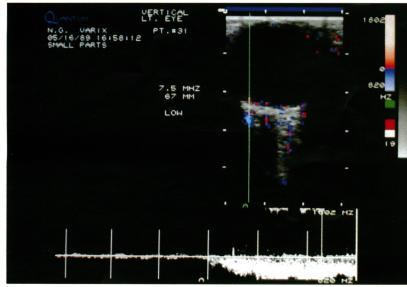

Colour Doppler imaging (CDI) is a recent development in ultrasonography. It allows simultaneous two-dimensional structural imaging and Doppler evaluation of blood flow. Quantitative information on flow velocity is obtained by pulsed Doppler spectral analysis, the colour information being used to choose the vessel of interest. Using this technique the authors examined a patient with an orbital varix previously diagnosed by clinical findings and computed tomography. Dynamic evaluation with real-time direct imaging of flow facilitated the diagnosis of this orbital disorder without the need for any contrast material. This technique may prove to be a useful adjunct to computed tomography for the evaluation of suspected vascular lesions of the orbit.

彩色多普勒成像(CDI)是超声检查领域的一项最新进展。它能够同时进行二维结构成像以及对血流进行多普勒评估。通过脉冲多普勒频谱分析可获取有关流速的定量信息,颜色信息则用于选择感兴趣的血管。作者运用这项技术对一名先前经临床检查和计算机断层扫描诊断为眼眶静脉曲张的患者进行了检查。通过对血流进行实时直接成像的动态评估,无需使用任何造影剂即可辅助诊断这种眼眶疾病。这项技术可能会被证明是计算机断层扫描在评估可疑眼眶血管病变时的一项有用辅助手段。